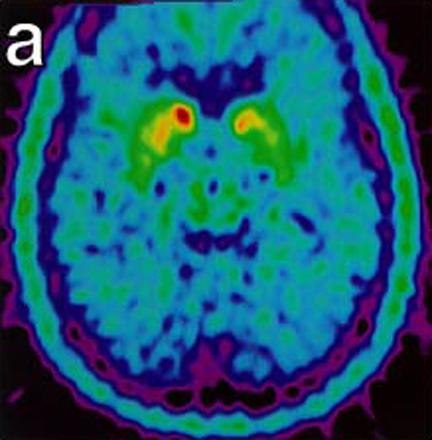

These images show malfunctioning nerves consistent with Parkinson's. The second image (below) shows increasing activity after implantation. "18-Fluoro-DOPA Positron Emission Tomography Studies. (a) Pre transplant uptake study showing decrease nerve terminal density in the striatum, worse on left (right on picture), consistent with Parkinson’s disease. (b) Post transplant study with increase activity of marker at the site of micro-injections in left putamen." (Levesque et. al.)